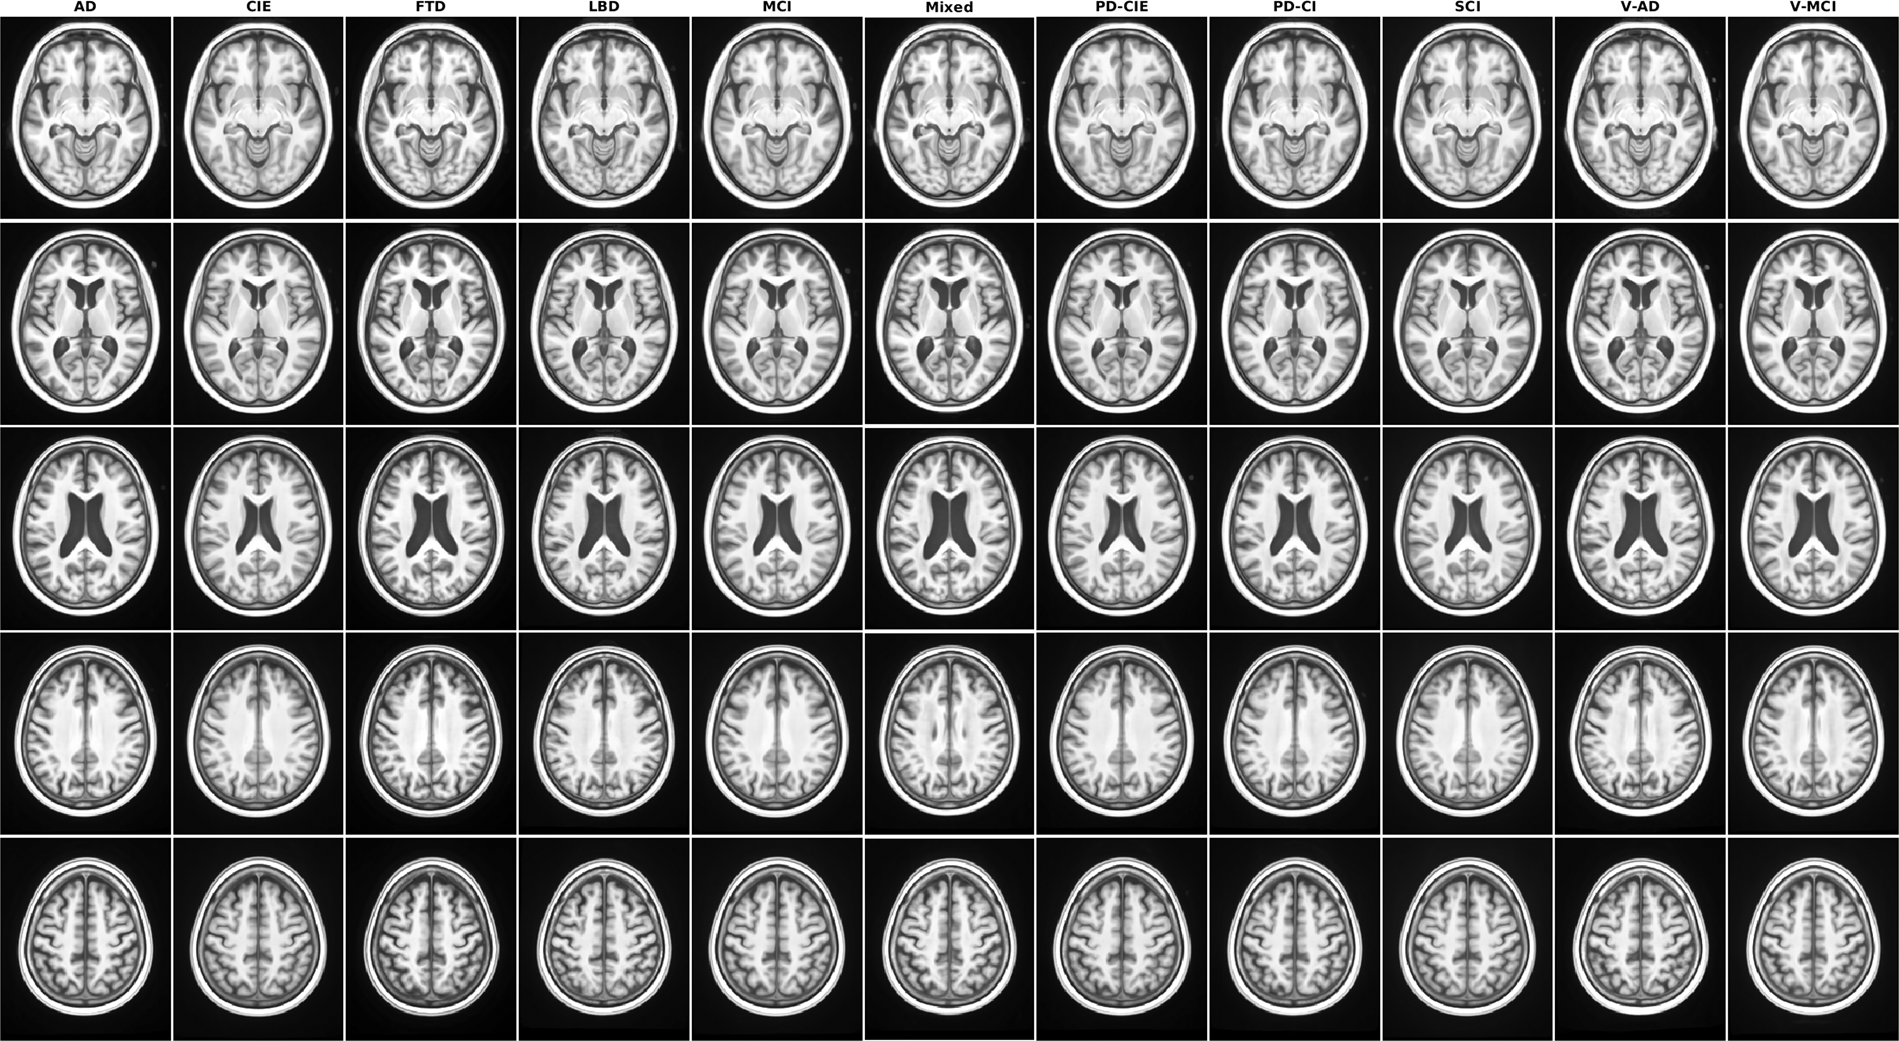

Axial slices of T1w average templates for all diagnostic groups.